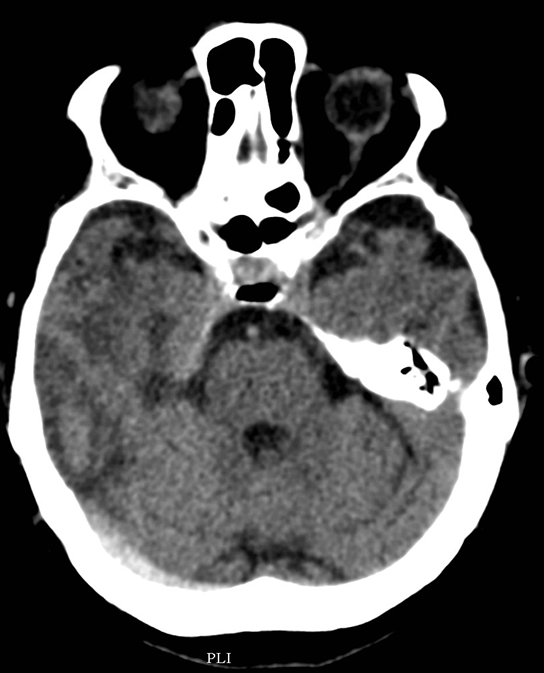

The key question whether the patient ha intracranial hematoma, which causes mass effect and later leads to vasoconstriction. In the presence of open skull fracture signed by liquorrhea severe infection and herniation might occur. To exclude intracranial hemorrhage CT is the modality of choice.

All three types of intracranial hematoma can occur as a result of head trauma:

• Rupture of the meningeal arteries may give rise to an epidural hematoma. At the site of the hematoma skull fracture can be observed.

4.Middle-aged man some days after direct head trauma. On noncontrast CT a lens-shaped, slightly inhomogenous epidural hematoma can be seen, that causes compression of the right lateral ventricle (left panel). In bone window skull fracture without dislocation can be found at the site of the hematoma (right panel).

• Subdural bleeding is caused by injured bridging veins (elongation, tears) e.g. when a sudden deceleration occurs. This type of injury generally is not associated with a fracture.

5. A middle aged chronic alcoholic male. On unenhanced CT a typical crescent shape subdural hemorrhage is seen on both sides. Because of its etiology it extends across suture lines.

• Subarachnoid hemorrhage develops after vascular injury or aneurysm rupture.

6. Middle aged female fell of a ladder. On the unenhanced CT scan the basal cisterns are filled corresponding to a subarachnoid hemorrhage.